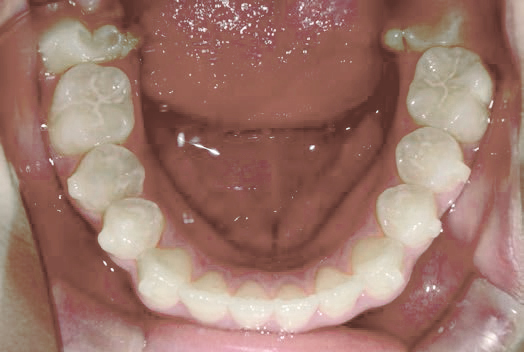

Before

歯がガタガタに並んでいて、前歯の真ん中の位置が少し左にずれていました。

奥歯が生えるためのスペースが足りず、永久歯が生えて来られない状況が確認できました。

また、飲み込むとき下くちびるに力が入ってしまうクセが見られ、お顔全体の成長が遅れている様子が確認できました。